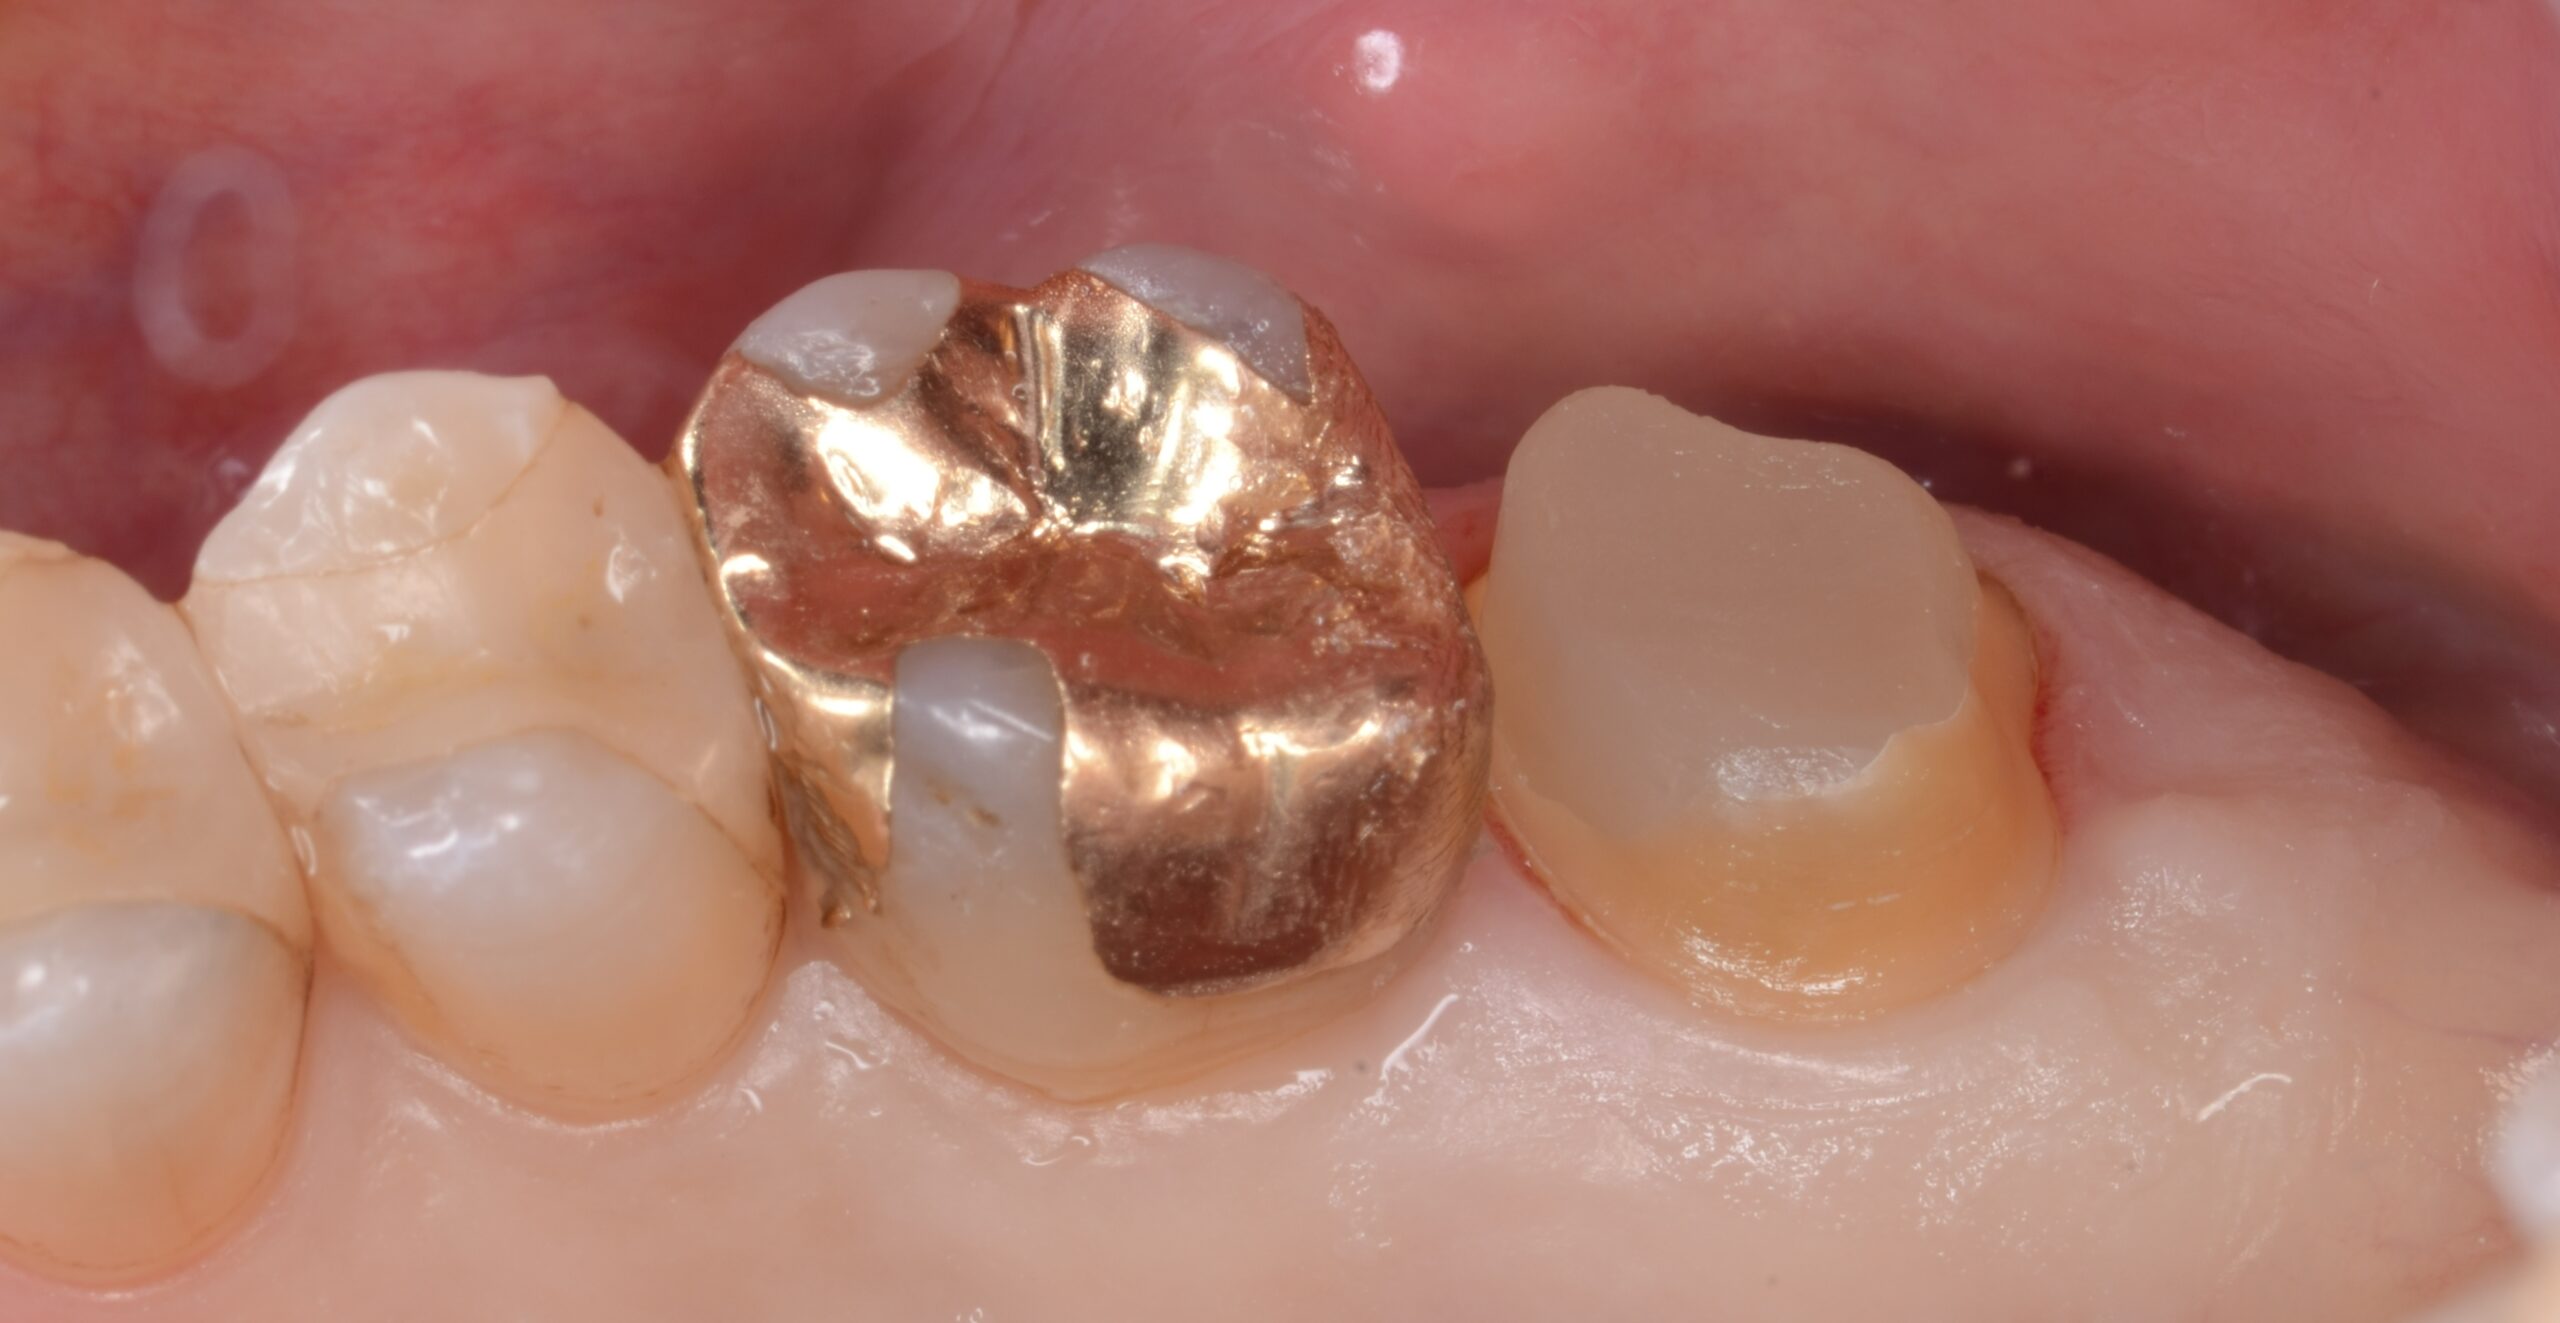

after

3. 右上6・7の補綴治療による形態回復と清掃性の改善

第二大臼歯遠心部の過剰歯肉を楔状に切除し、歯肉形態を整えることでポケットの減少および清掃性の改善を図った。術後は良好な歯肉形態が獲得され、遠心部のプラークコントロールが容易となった。